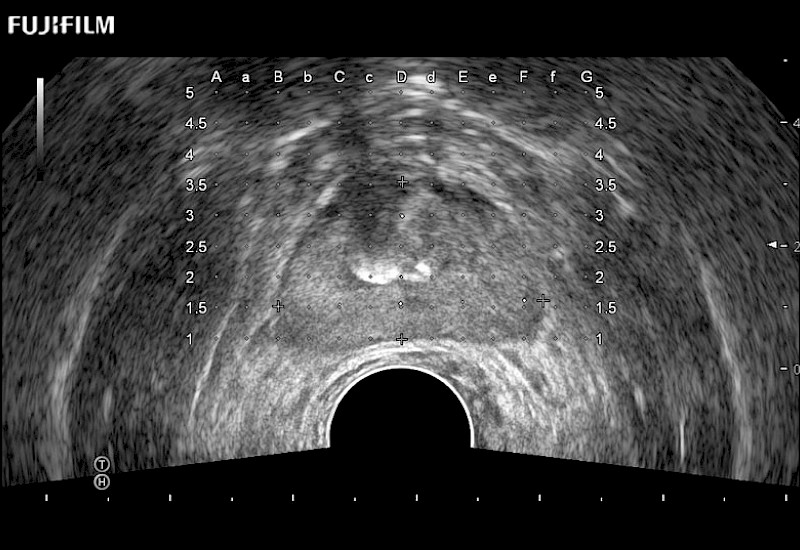

Ideal transducer for Transperineal Biopsy, Hydrogel Spacer Placement, Brachy LDR & HDR, Cryo, and MPMRI procedures.

Main Specifications: